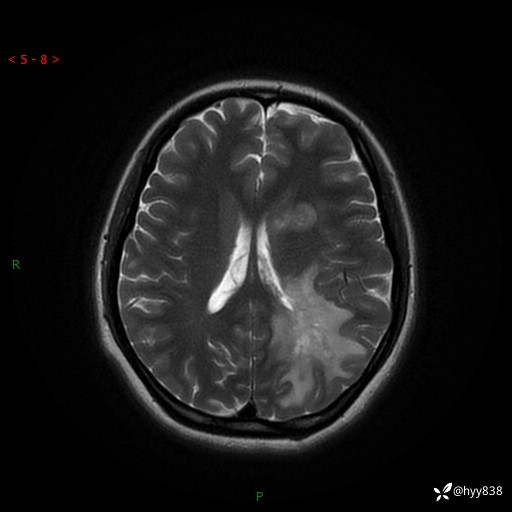

颅脑MRI平扫+增强